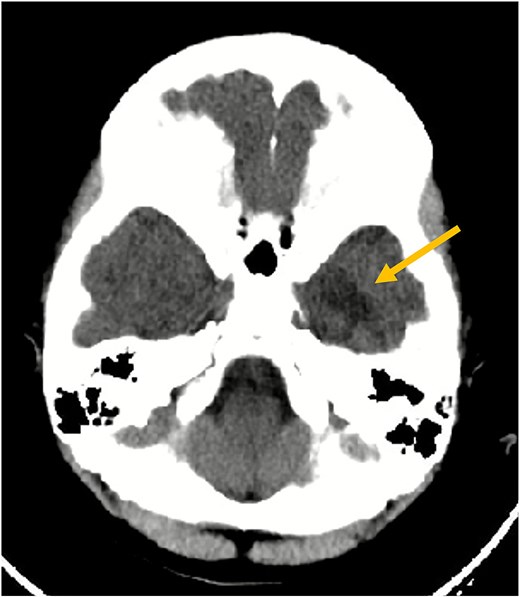

A 7-year-old girl with no significant past medical history presented after two minor head trauma events on the same day affecting her left temporal region. The first was a slip causing a direct impact, followed by a push from her sibling, after which she developed vomiting episodes. Physical and neurological examinations were normal. A non-contrast computed tomography (CT) scan excluded acute hemorrhage but revealed an ill-defined hypodense area in the left inferior temporal lobe.

Axial non-contrast CT scan of the brain. This image demonstrates an ill-defined hypodensity (arrow) in the left inferior temporal lobe (seen as a darker area). No acute intracranial hemorrhage or fracture was identified at the time of this initial scan.